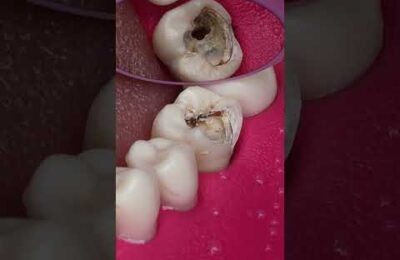

Dentist Looking Tooth Cavity #dentist #satisfying

Dentist Looking Tooth Cavity #dentist #satisfying #shorts.